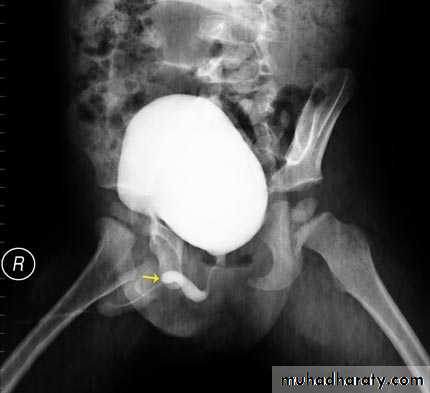

Voiding cystourethrogram (micturating cystogram)Retrograde urethrogram

If the bladder is involved, the wall is irregular because of inflammatory edema; advanced disease causes fibrosis resulting in a thick-walled small volume bladder.

Multiple strictures may be seen in the urethra.

Chronic pyelonephritis (reflux nephropathy)

Local reduction in renal parenchymal width (scar formation). The upper and lower calices are the most susceptible to damage from reflux.Dilatation of the calices in the scarred areas

Overall reduction in renal size partly from loss of renal parenchyma.

Dilatation of the affected collecting system

Vesicoureteric reflux may be demonstrated at micturating (voiding) cystography.